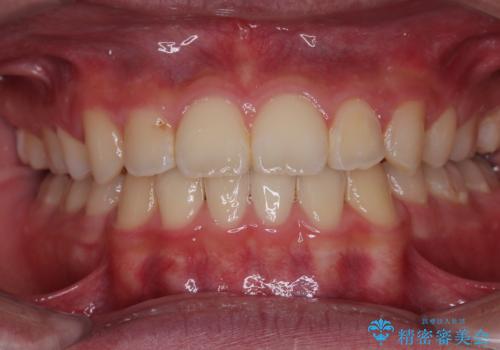

矯正歯科治療 → 上下顎前突(口ゴボ)

- デコボコと口元の突出感を改善 抜歯矯正治療